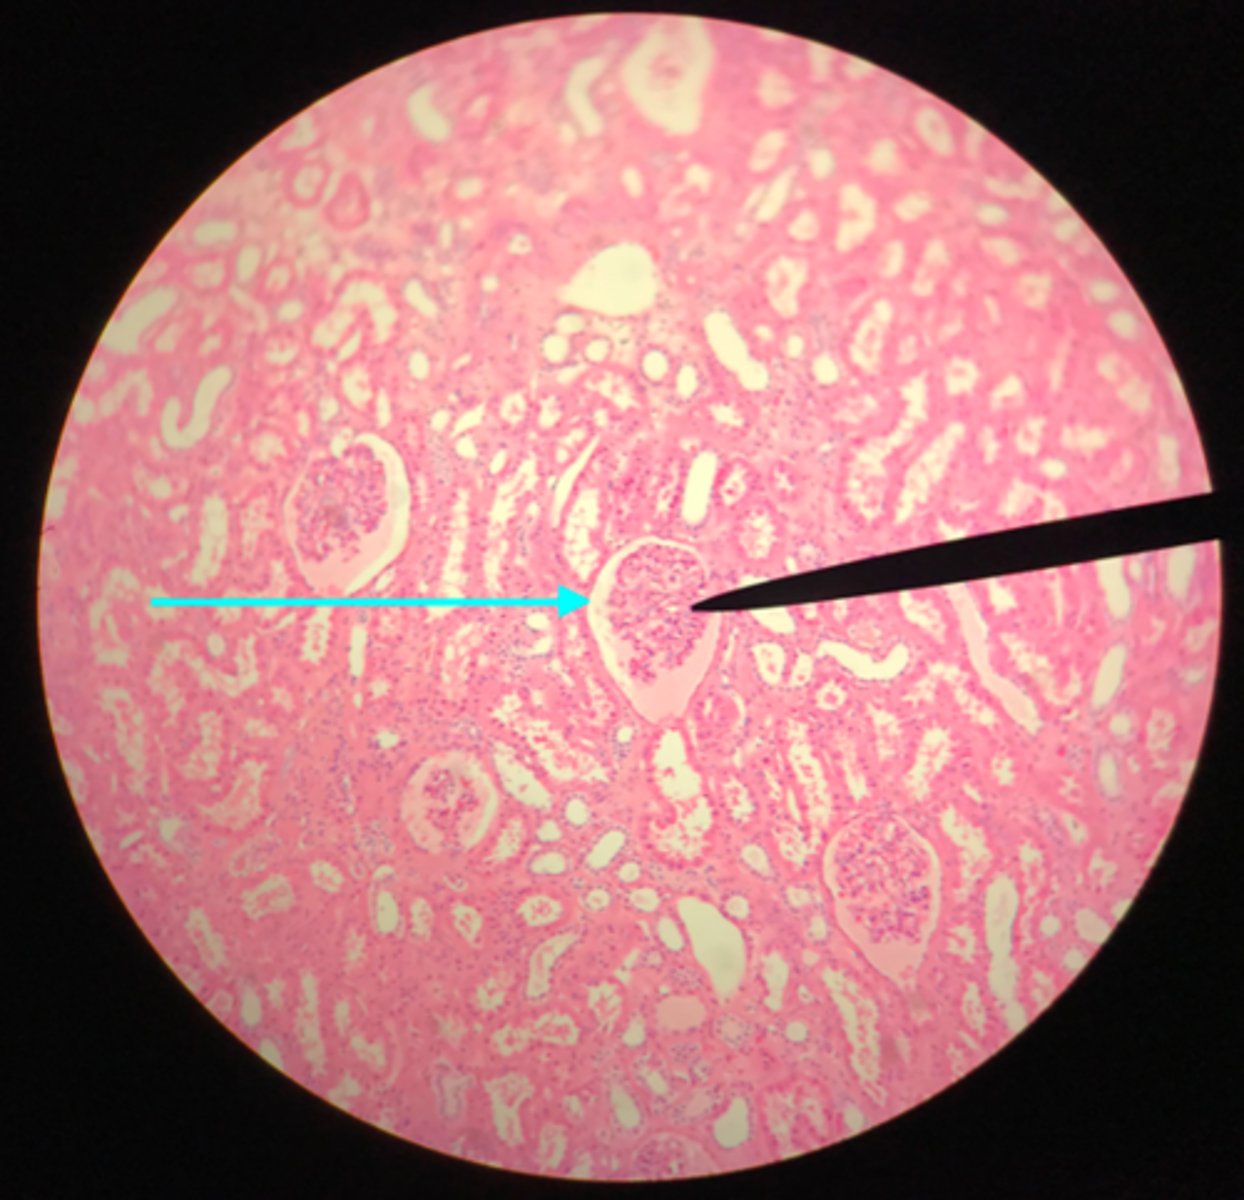

Cortex of the kidney

There are glomerular corpuscles present in the cortex. They are not present in the medulla

What layer of tissue of which organ is depicted on this slide? How can you tell?

Glomerular (Bowman's) capsule (in the cortex)

What structure of the kidney is the blue arrow pointing at?

Glomerulus

What structure of the kidney is the pointer placed on?

Renal tubules (in the cortex)

What structure of the kidney is the blue arrow pointing at?